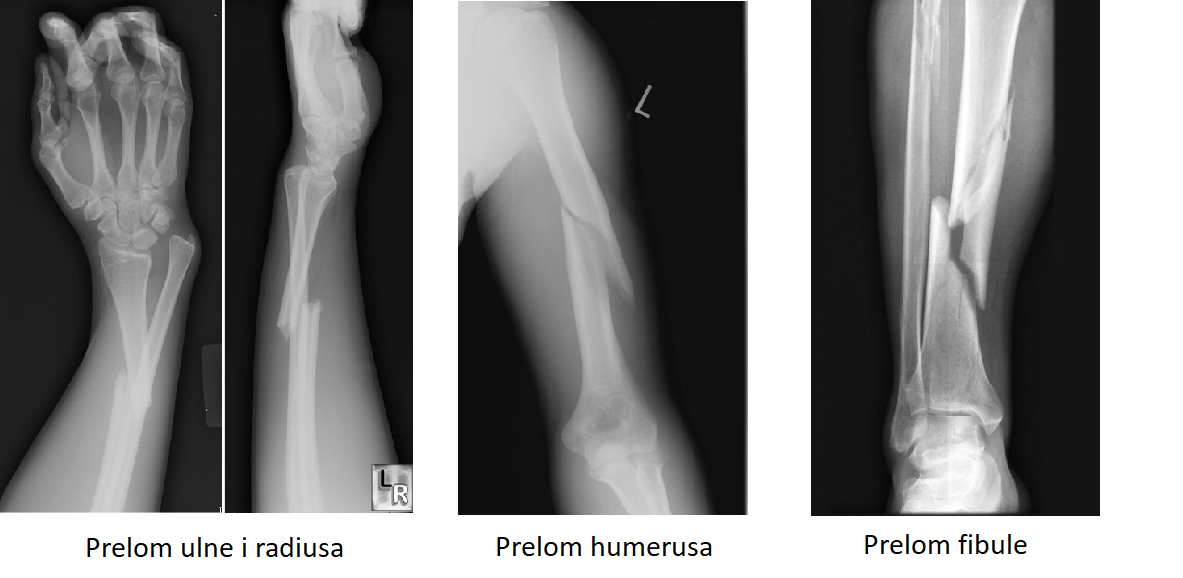

Najbolju informaciju o koštanom prelomu daje radiografska dijagnostika. Prelom se obavezno snima u dva pravca (anteroposteriorno i iz profila) a može i u dopunskim pravcima (kosi snimak). U Atlas opštoj bolnici obavlja se sva neophodna RTG dijagnostika za nekoliko minuta.